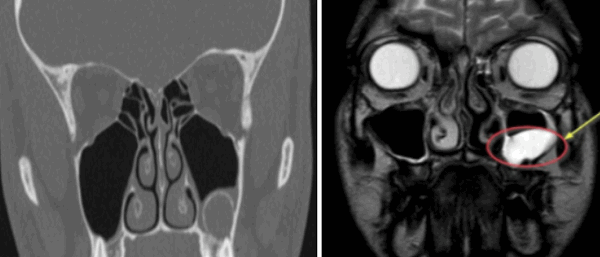

Слева — КТ-снимок одонтогенной кисты в верхнечелюстном синусе, справа — МР-фото образования (указано стрелкой) в гайморовой пазухе